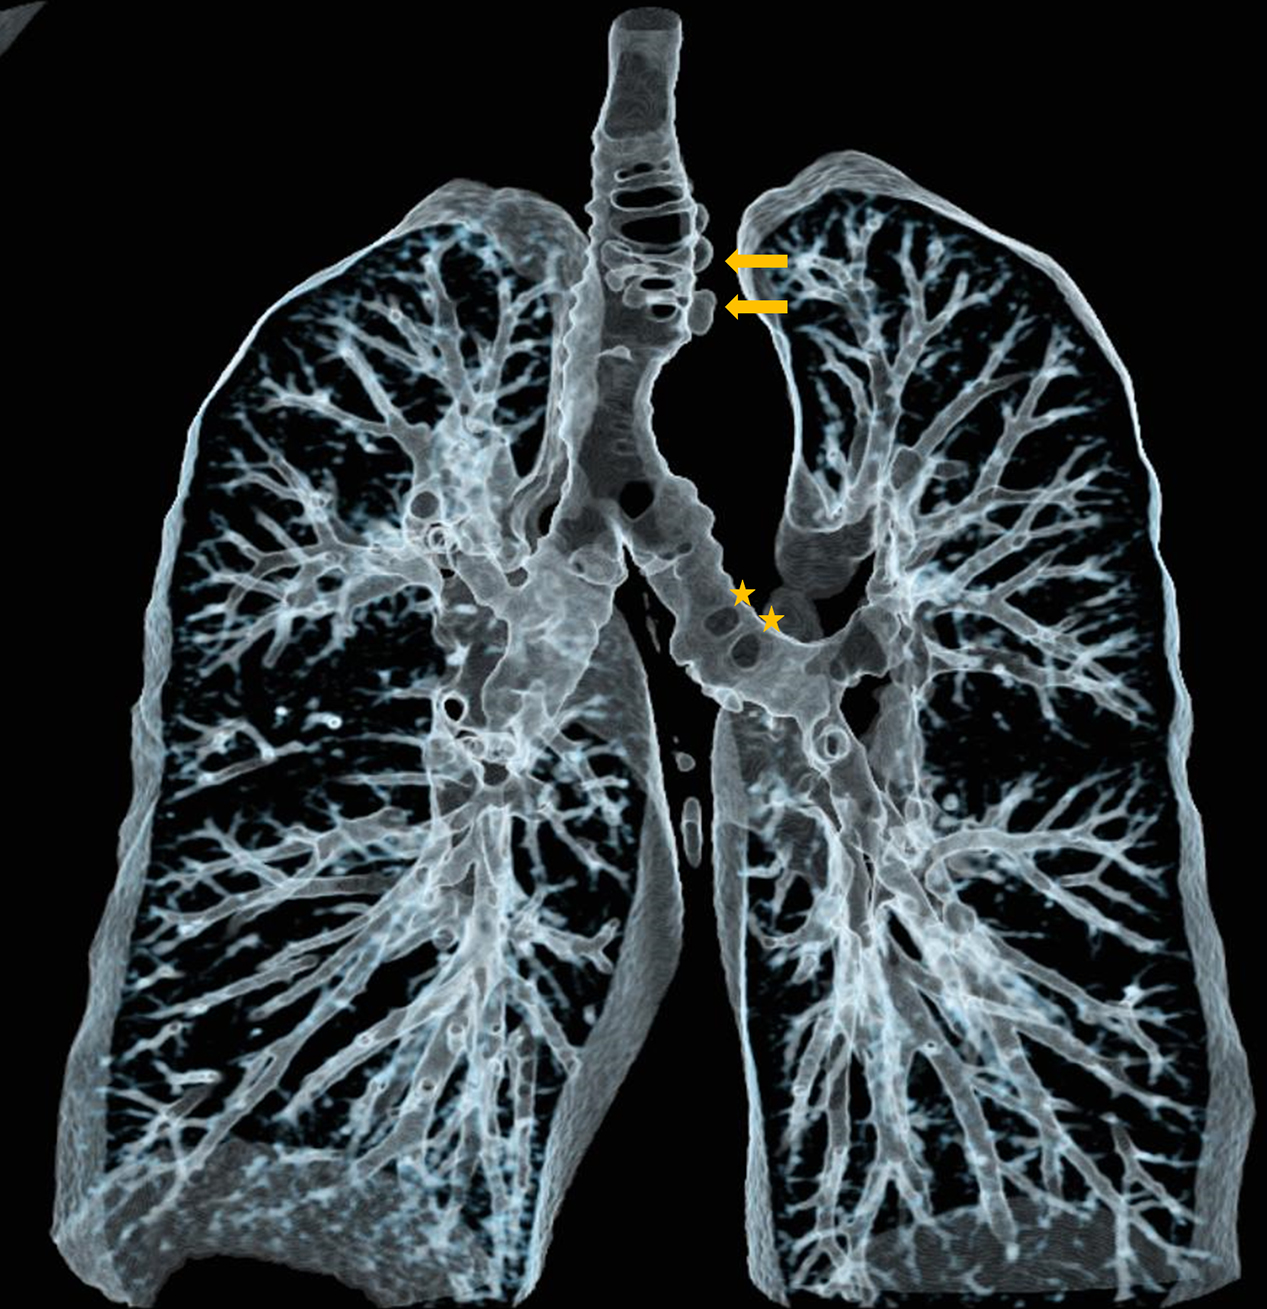

Figure 3

Virtual bronchography of thacheobronchial diverticulosis.